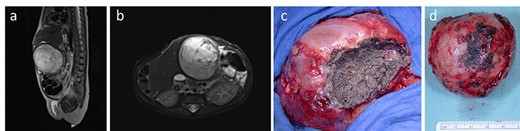

On the 31st postnatal day, the patient’s general condition progressively worsened. Echocardiographic examinations showed worsening of the cardiac biventricular function due to herniation of the right liver into the chest. On Day 38 of life, closure of the anterior diaphragmatic hernia through the abdominal wound was performed. After reduction of the liver and resection of the CDH sac, absence of the pericardium was noted. The diaphragmatic defect of 5 × 4 cm was closed with a Gore-Tex patch and the abdominal wall defect was covered with a Gore-Tex (Fig. 1).

The anterior thoracic defect (a) was covered with a Gore-Tex-Patch (b). After mobilization from the anterior mediastinal space, the liver assumed an irregular shape not allowing abdominal wall closure (c). The defect was temporarily covered by a skin Gore-Tex -Patch (d).